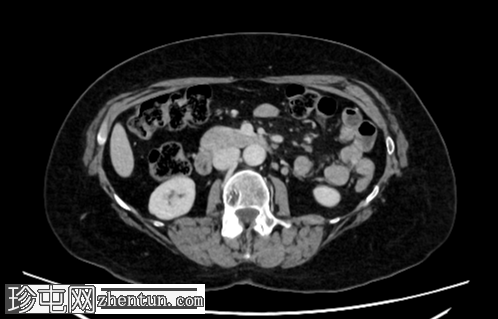

2.png

轴位增强扫描

门静脉期

右肾上极前外侧可见一边界清晰、分叶状、部分外生性病变,大小约4.0 x 6.8 cm(轴位)。病变内侧为无强化囊性成分,直径2.3 cm(动脉期和门静脉期平均密度均为13 HU);外侧为强化实性成分,直径4.5 cm(动脉期和门静脉期平均密度分别为68 HU和78 HU)。病灶内可见多处小钙化灶。病灶毗邻肝右叶,但未见侵犯肝实质的证据。肾静脉和下腔静脉通畅。肾门水平可见数个小的主动脉腔静脉淋巴结和腔静脉后淋巴结,其中最大的腔静脉后淋巴结短轴直径为7毫米。

右肾中极前缘可见10毫米Bosniak II型囊肿,双侧肾盂旁可见囊肿。右肾下极可见两处肾皮质缺损。肝脏第8段可见5毫米囊肿。未见远处转移。L2椎体可见血管瘤。